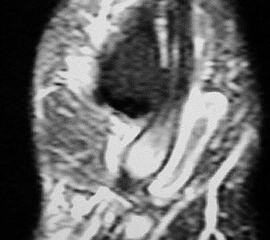

Aktivierte Coalitio der medialen Facette des Subtalargelenks im MRT.

Abbildung 28

Die häufigeren Coalitiones der medialen Facette des Subtalargelenks können auf der a.p. Aufnahme des Sprunggelenks erkennbar sein. Ein indirekter Hinweis ist das C-Zeichen in der seitlichen Aufnahme 60. Zusätzliche Projektionen wie der Harris- View haben durch das CT ihre Bedeutung verloren 6162. Das CT ist heute das Standardverfahren zum Nachweis knöcherner Coalitiones.

Das MRT findet Anwendung, um fibröse Coalitiones nachzuweisen, bzw. um nicht eindeutige knöcherne Befunde zu kontrollieren 6364. Dies gilt insbesondere auch für weitere Pathologien des Subtalargelenks, welche einen reaktiven Peronealsehnenspasmus auslösen können.